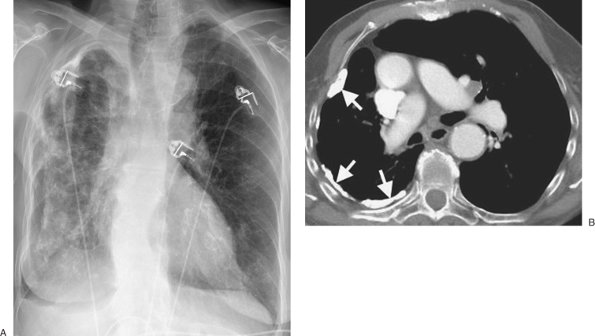

FIGURE 9-5. Cerebrospinal fluid leak into pleural space. A: PA chest radiograph of a 42-year-old man who recently underwent partial corpectomy of the thoracic spine at several levels shows complete opacification of the right hemithorax and shift of the mediastinum to the left. B: Non–contrast-enhanced CT shows a large right pleural effusion, collapse of the right lung, mediastinal shift to the left, findings of corpectomy, and continuity of fluid from the spine into the pleural space (arrow).